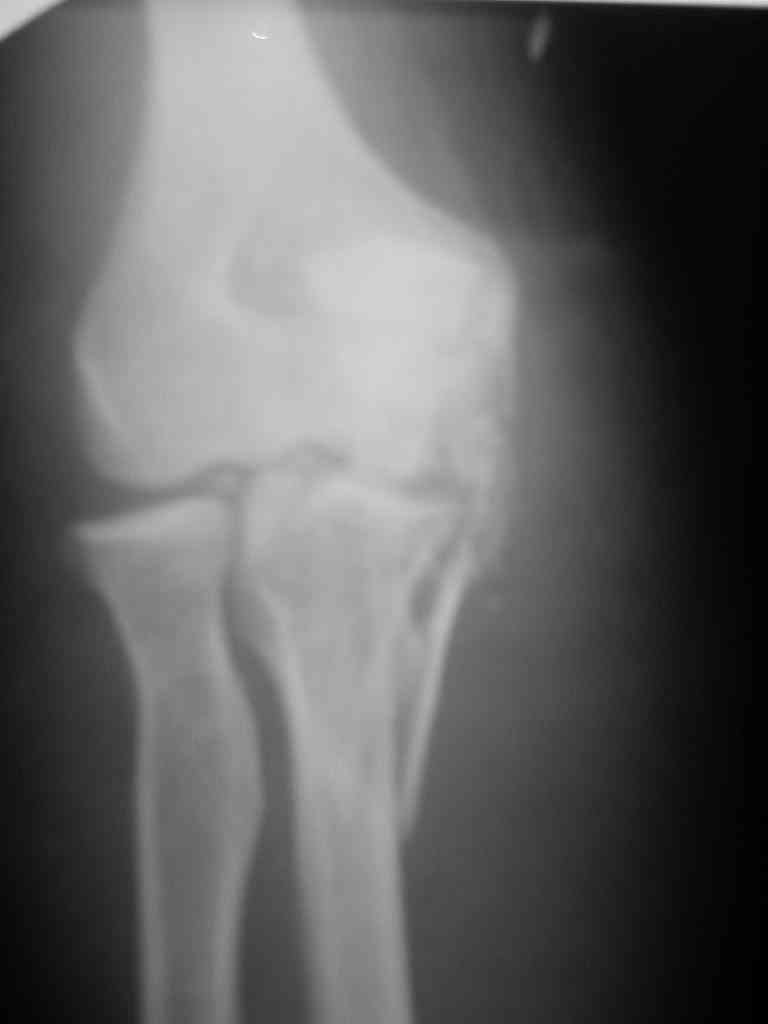

Снимки вот еще какие есть (наши лаборанты пытались сделать что то)

При самом большом к Вам уважении, Сергей Анатольевич, не соглашусь. У меня, после того, как добавили "прямой" снимок, сомнений не осталось. Венечный сломан наверняка. Но чтобы судить, насколько это критично для стабильности, нужно иметь строго боковую проекцию. И при этом помнить, что на него крепятся медиальные связки.

Прикрепляю снимок, где обведен фрагмент, несущий на себе венечный отросток (весь он смещён с этим фрагментом или частично - без качественной боковой проекции судить сложно), и отдельно на снимке обведено "ложе", от которого он сместился.